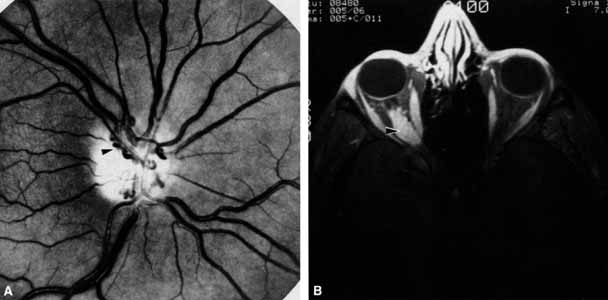

Optociliary shunts (Fig. 12A) develop as a result of long-term obstruction of the central retinal vein. This may occur secondary to optic nerve meningiomas,13 optic nerve gliomas,14,15 optic nerve meningoceles,16 central retinal vein occlusions,17 optic nerve sarcoidosis,18 craniosynostosis,19 optic nerve arachnoid cysts,20 optic disc drusen,21 and papilledema.15 Congenital optociliary shunts, which are exceedingly rare, have not been associated with optic neuropathy or orbital disease.22,23 The presence of optic nerve pallor, poor acuity and optociliary shunts generally implies an optic nerve meningioma in the absence of other funduscopic findings (Fig. 12B).13

Fig. 12 A. Optociliary shunt vessels (arrow) are present on the surface of an atrophic optic disc. The patient's visual acuity was hand motions. The patient demonstrates 2 mm of proptosis. B. Gadolinium-enhanced, fat-suppressed magnetic resonance imaging (MRI) demonstrates an intraorbital optic nerve sheath meningioma (arrow).